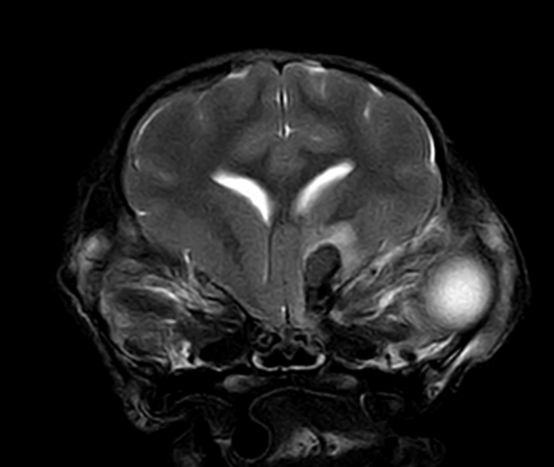

3T MRI

기존 본원에서 이용하던 1.5T 장비와 비교하여 높은 해상도와 빠른 스캔 시간(촬영 부위 당 30분 미만)으로 MR 촬영 시 환자의 마취 부담을 줄일 수 있습니다.

3T MRI는 국내 동물병원에서 최상급 촬영 장비에 해당하며 본동물의료센터의 MRI는 3T MRI 중에서도 하이엔드급 장비(Philips Ingenia)를 사용하고 있습니다.

소뇌 경색(개)

01뇌 MRI

· 뇌신경계 질환의 정확한 감별 및 조기진단

· 뇌수두증, 뇌출혈, 뇌종양, 뇌수막염, 소뇌탈출 등

· 전정계(중이, 내이) 질환의 진단